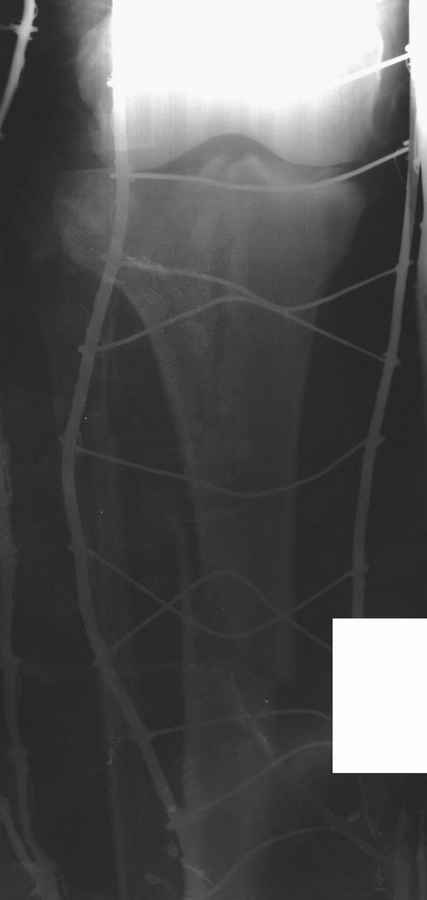

Пациенту сделали КТ - ухитрились сделать на шине Белера (не давал положить прямую ногу) - срезали передний отдел. Планируется на пятницу (24.12) на операцию - синтез длинной мыщелковой LCP-пластиной Synthes :). Отек ближе к слову умеренный (окружность голени +4 см по сравнению со здоровой). КТ и снимок на вытяжении прилагаются.

Спасибо всем за высказанные мнения, о результатах обязательно проинформирую.